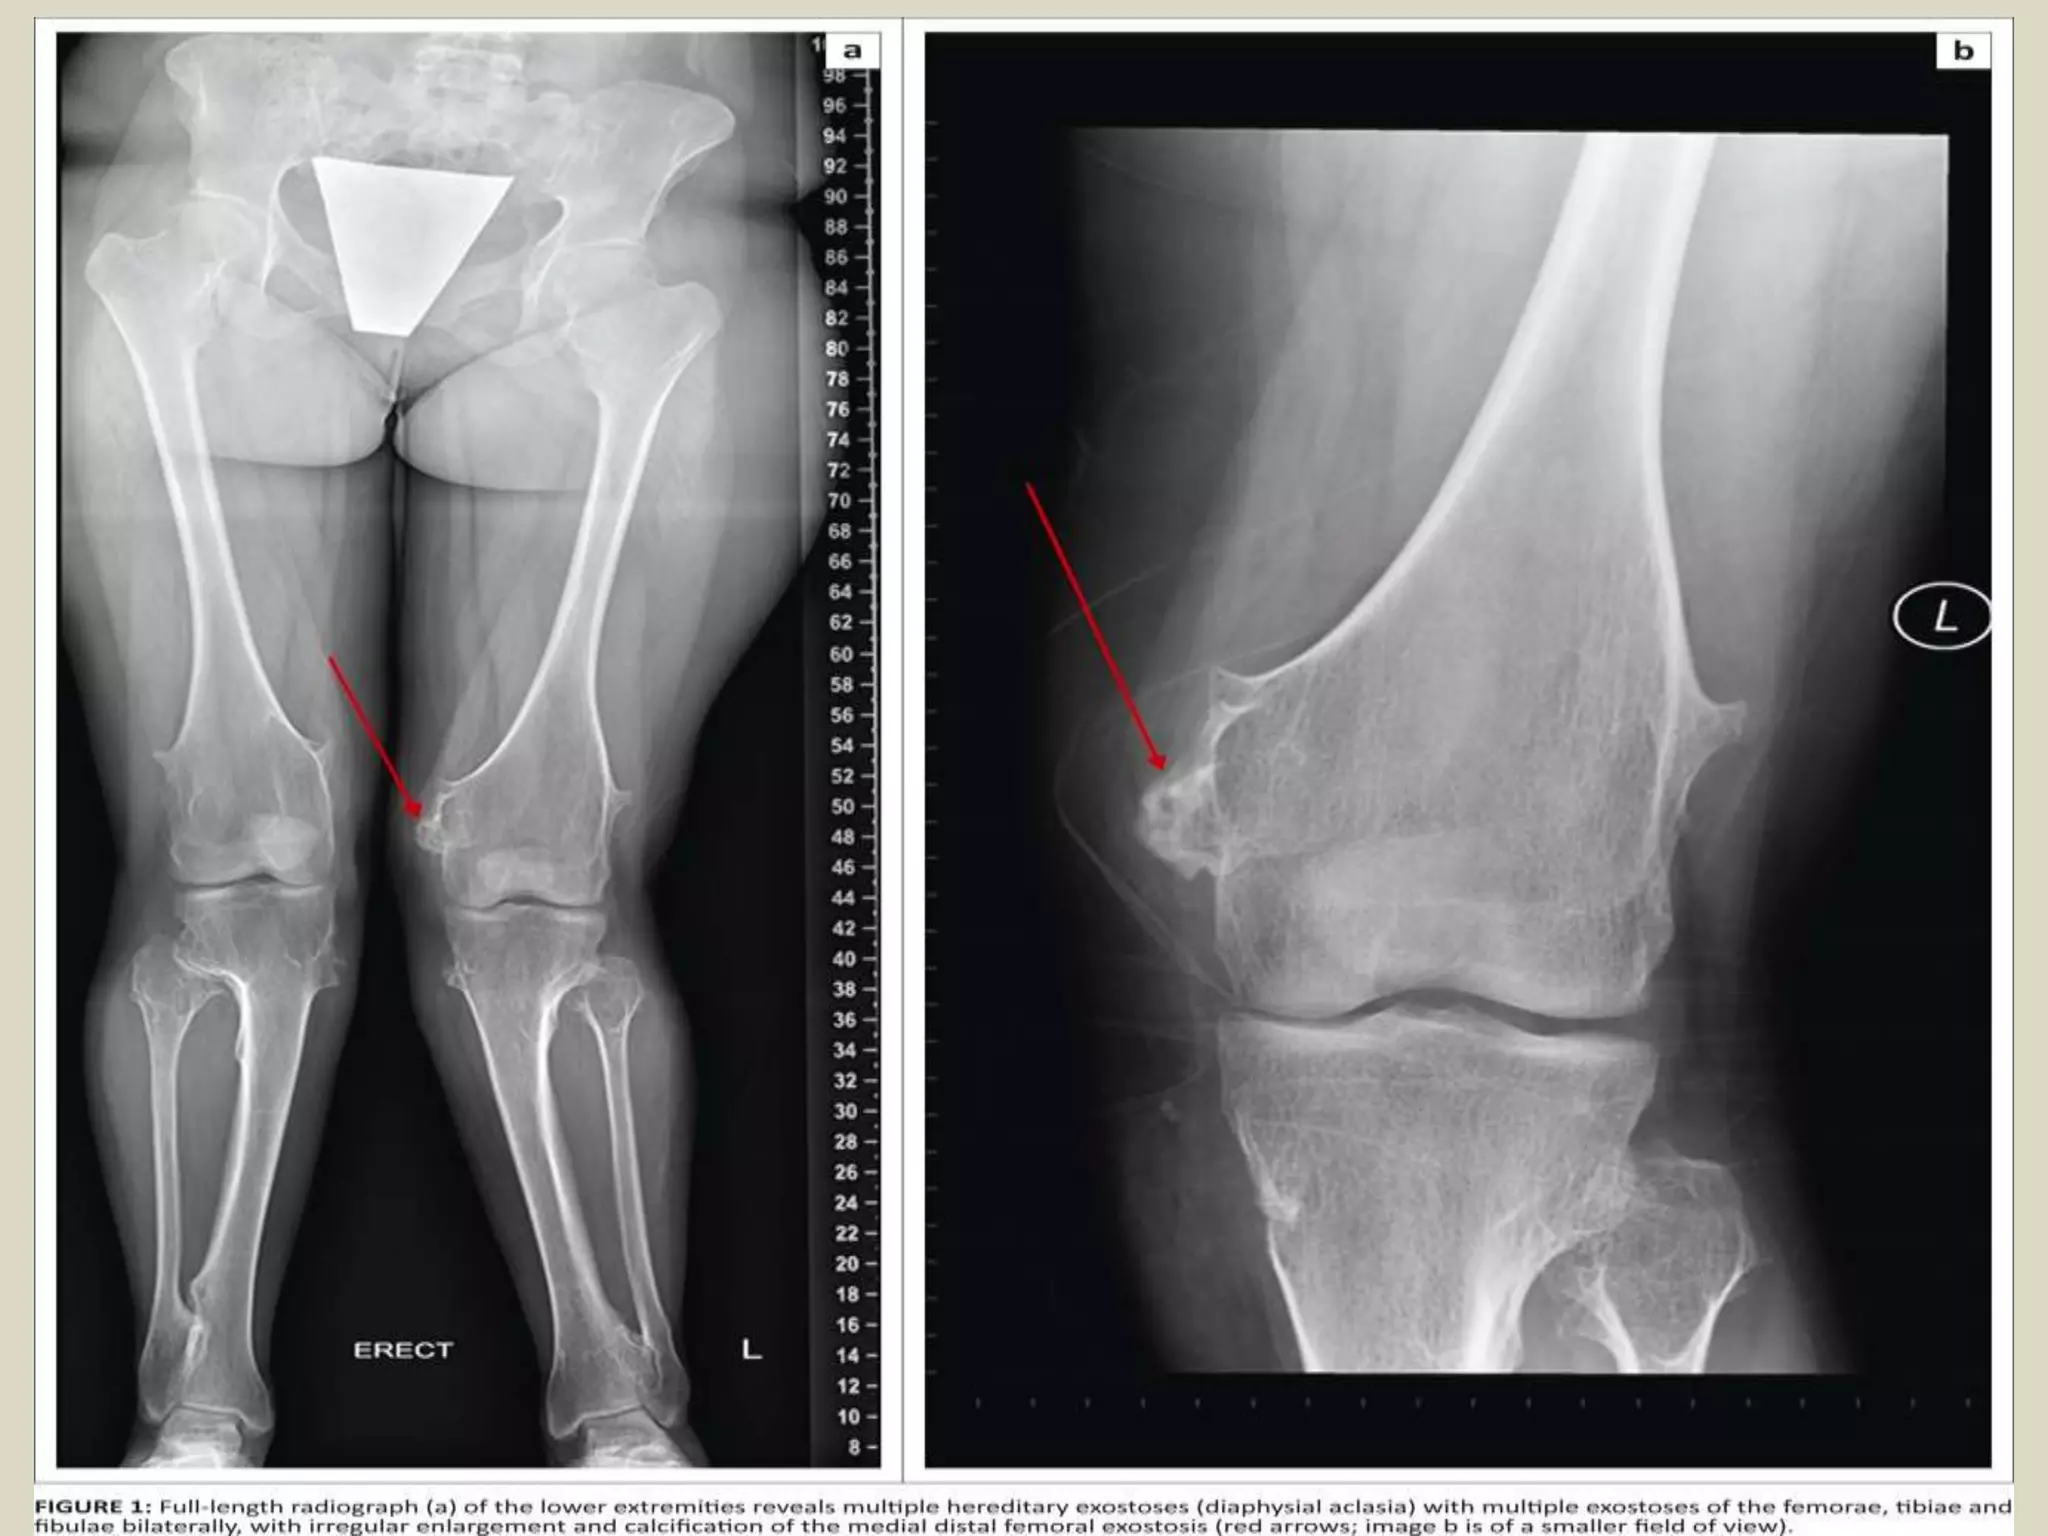

-Osteochondroma may be solitary or multiple, the latter occurring in the setting of hereditary multiple

- Hereditary multiple exostoses (HME) is an autosomal dominant genetic disorder, and has prevalence

- Patients with HME come to medical attention at the younger age , usually during first decade, because

- Most common site of involvement is the metaphyseal region of distal femur, upper humerus, upper tibia

- Bulbous lesions on X rays, and they a narrow or broad (sessile) osseous radiosense stalk, which is attached

- The characteristic feature is a projection of the cortex in continuity with the underlying bone.

- Excessive cartilage type flocculent calcification should raise the suspicion of malignant transformation.

- CT scan or MRI images typically show continuity of the marrow space into the lesion. A thick cartilaginous

cap rises suspicion of malignant transformation.

(A and B) In the knees, radiographs showing multiple

lesions in the proximal regions of the tibias and fibulas.